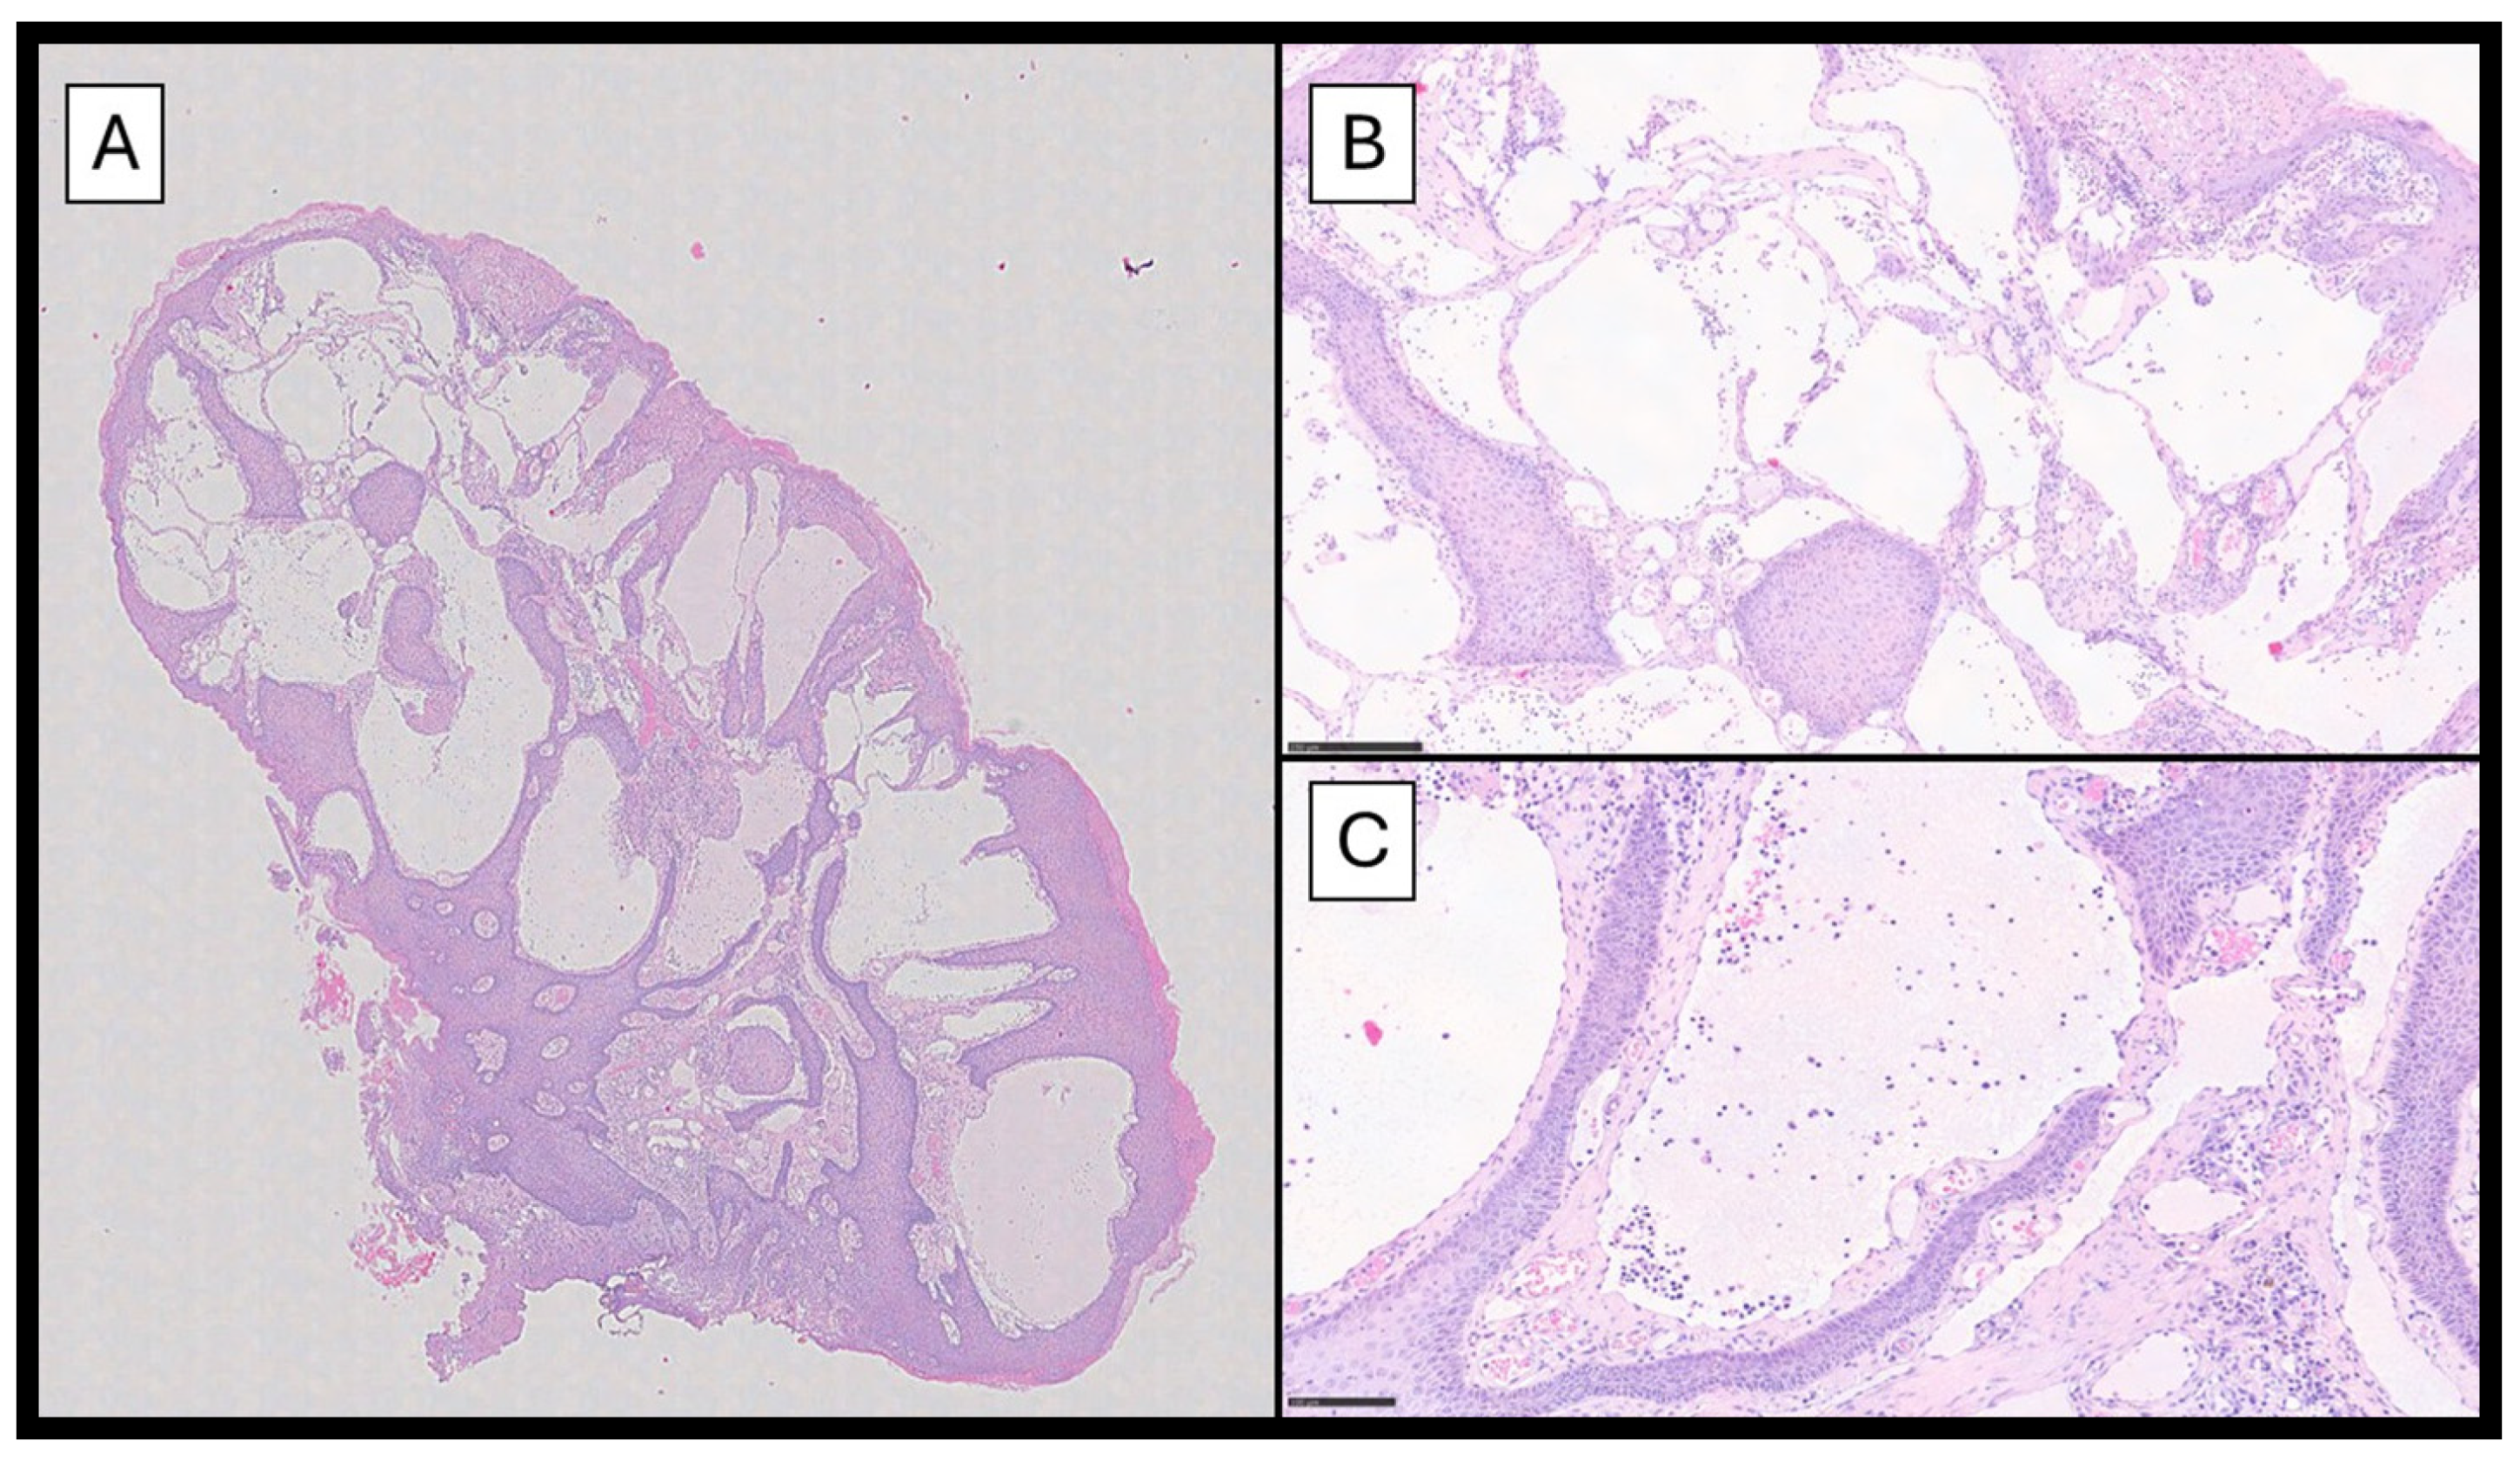

Histopathological examination showed a papillomatous lesion characterized by hyperkeratosis, focal erosion, and dilated vessels lined by flat endothelial cells without atypia containing lymphocytes and serum (Figure 2A–C); furthermore, the lymphatic nature of the vessels was confirmed by immunohistochemical reaction with Podoplanin (D2-40) (Figure 3).

Figure 2. (A) A histopathological photomicrograph showing a papillomatous lesion characterized by hyperkeratosis, focal erosion, and multiple dilated vessels (hematoxylin–eosin, original magnification 4×). (B) An image with higher magnification showing details of the dilated lymphatic vessels lined by flat endothelium containing some lymphocytes and serum (C) (hematoxylin–eosin, original magnification 10× and 20×).